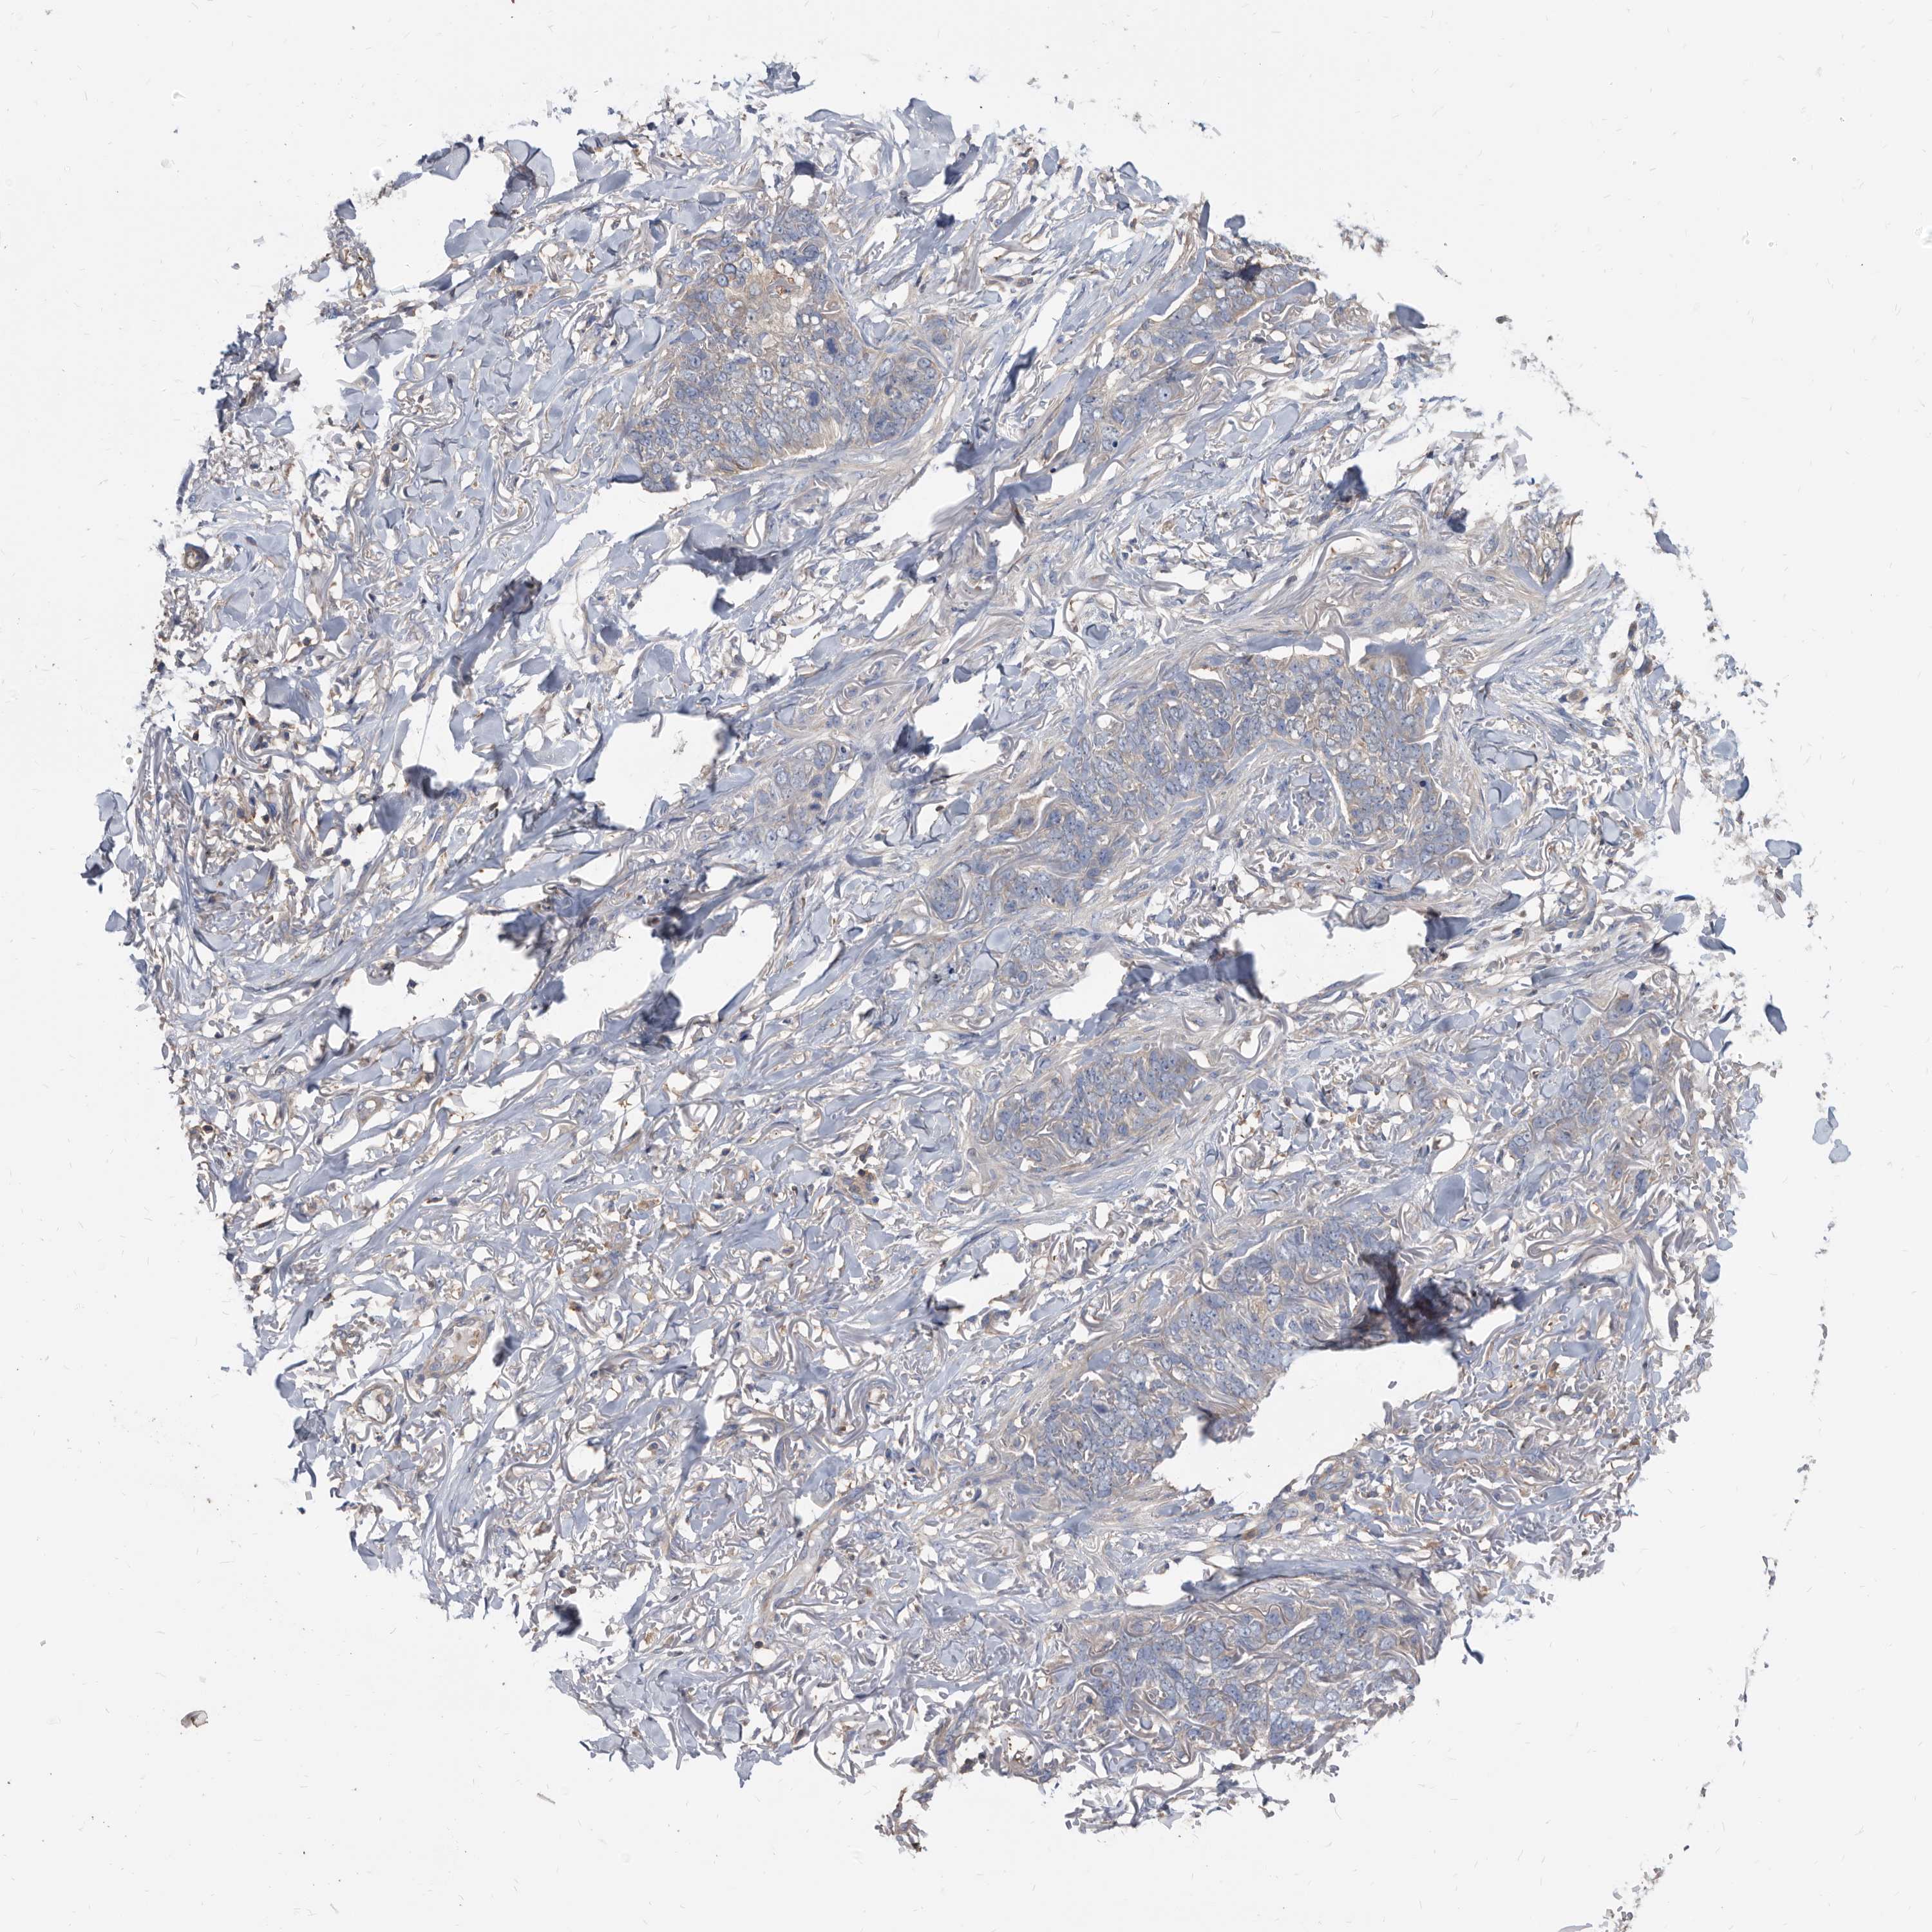

SKIN CANCER - Protein expressioni

A mouse-over function shows sample information and annotation data. Click on an image to view it in a full screen mode. Samples can be filtered based on level of antibody staining by selecting one or several of the following categories: high, medium, low and not detected. The assay and annotation is described here.

Each image is clickable and will lead to virtual microscopy that enables deeper exploration of all samples and also displays staining intensity scores, fraction scores and subcellular localization as well as patient and tissue information for each sample.

Antibody HPA029700

Antibody HPA029701

Antibody HPA029702

Antibody HPA029703

Staining

High

Medium

Low

Not detected

Intensity

Strong

Moderate

Weak

Negative

Quantity

>75%

75%-25%

<25%

None

Location

Nuclear

Cytoplasmic/membranous

Cytoplasmic/membranous,nuclear

Basal cell carcinoma

Squamous cell carcinoma, NOS

Squamous cell carcinoma, metastatic, NOS